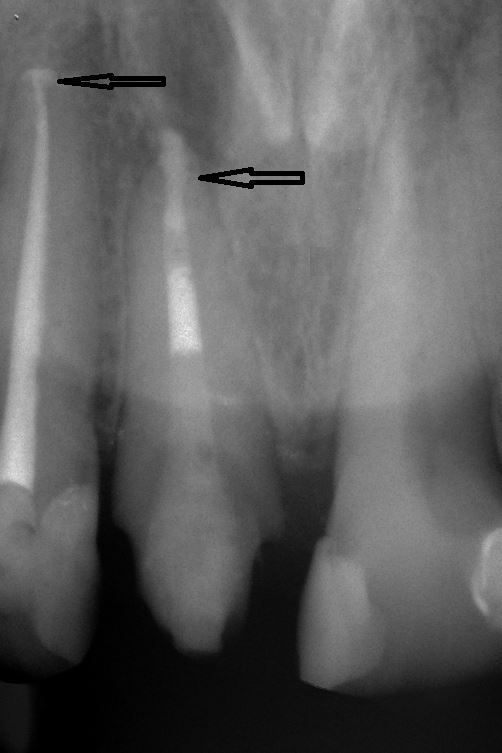

Unter örtlicher Betäubung ist die Behandlung in der Regel schmerzfrei. Nach Entfernung der Karies und nach der Schaffung eines Zugangs in den Zahn werden die Kanaleingänge dargestellt und die Länge jedes einzelnen Kanals wird möglichst exakt unter Anwendung von Röntgen ausgemessen. Abhängig vom zu behandelten Zahn kann die Anzahl der Kanäle stark variieren.

Mit Hilfe der elektronischen Längenmessung und digitalen Röntgenbildern können die Länge und Krümmung der Kanäle bestimmt und der Verlauf beurteilt werden.